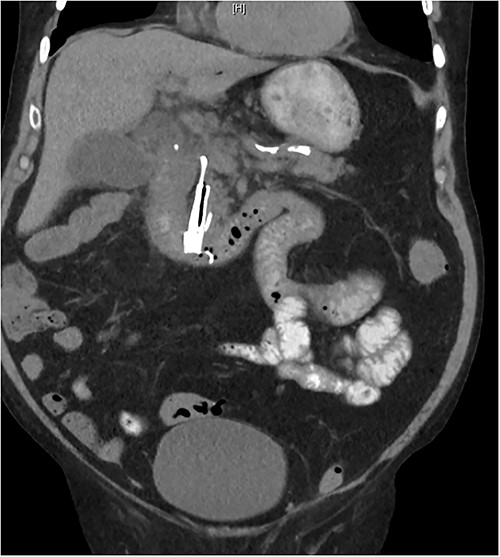

A 98-year-old male from a high-level care nursing home presented to the emergency department with abdominal pain, vomiting and faecal incontinence. His medical history included atrial fibrillation, transient ischaemic attack, chronic kidney disease, peripheral vascular disease, hypertension, gout and osteoarthritis. His surgical history included previous endoscopic retrograde cholangiopancreatography (ERCP) for acute biliary pancreatitis 30 months prior with insertion of a 4 cm × 10 mm metal biliary stent with an internal anchoring 7 Fr × 4 cm double pigtail plastic stent (Fig. 1). His Charlson comorbidity index was 3 with an American Society of Anaesthesiologists’ (ASA) classification of IV.

On presentation, there was no signs of shock, with a blood pressure of 152/70, heart rate of 88 and oxygen saturations of 94% on room air. A temperature of 38.1°C, however, was noted and physical examination revealing a distended abdomen with right lower quadrant tenderness. He had no peritonism and digital rectal examination showed an empty rectum. Biochemical investigations showed a white blood cell count of 20.00 × 109/L, C-reactive protein level of 126 mg/L, eGFR of 32 ml/min/1.73 m2, creatinine of 153 umol/L; he had normal liver function tests, coagulation profile and electrolytes. A computed tomography (CT) abdomen and pelvis with intravenous contrast revealed a distally migrated metallic biliary stent located in the terminal ileum with mildly dilated loops of distal small bowel indicating early or incomplete small bowel obstruction (Fig. 2).